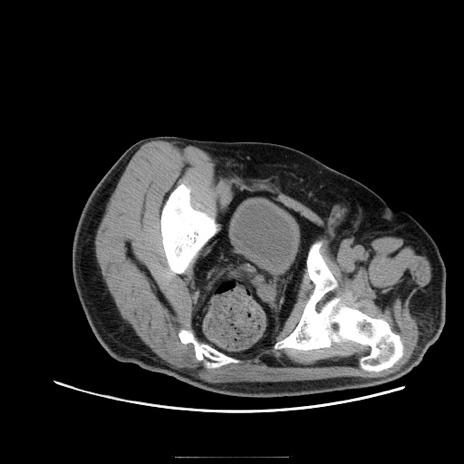

症例22(横断像)

【症例】50歳代男性

【主訴】腹痛

【現病歴】AVMからの被殻出血のため回復期リハ病棟入院中。 本日午後3時頃急に下腹部痛が出現した。

【既往歴】AVM、被殻出血、虫垂炎、高血圧

【身体所見】意識晴明、左半身不全麻痺、会話の理解は良好、36.5°C、腹部:膨隆、全体に板状硬、下腹部正中に圧痛点あり、反跳痛-、筋性防御不明、右下腹部にope scar

【データ】WBC 9400、CRP 0.06